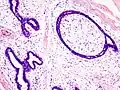

Histopathologic image of breast fibroadenoma showing proliferation of intralobular stroma compressing and distorting the epithelium. H&E stain. -

Fibroadenoma of the breast is a benign tumor composed of a biplastic proliferation of both stromal and epithelial components.[12][13] This biplasia can be arranged in two growth patterns: pericanalicular (stromal proliferation around epithelial structures) and intracanalicular (stromal proliferation compressing the epithelial structures into slit-like spaces).

These tumors characteristically display hypovascular stroma compared to malignant neoplasms.[2][14][9] Furthermore, the epithelial proliferation appears in a single terminal ductal unit and describes duct-like spaces surrounded by a fibroblastic stroma. The basement membrane is intact.[15]